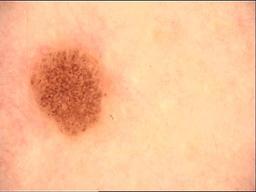

Skin lesion datasets provide essential information for understanding various skin conditions and developing effective diagnostic tools. They aid the artificial intelligence-based early detection of skin cancer, facilitate treatment planning, and contribute to medical education and research. Published large datasets have partially coverage the subclassifications of the skin lesions. This limitation highlights the need for more expansive and varied datasets to reduce false predictions and help improve the failure analysis for skin lesions. This study presents a diverse dataset comprising 12,345 dermatoscopic images with 40 subclasses of skin lesions, collected in Turkiye, which comprises different skin types in the transition zone between Europe and Asia. Each subgroup contains high-resolution images and expert annotations, providing a strong and reliable basis for future research. The detailed analysis of each subgroup provided in this study facilitates targeted research endeavors and enhances the depth of understanding regarding the skin lesions. This dataset distinguishes itself through a diverse structure with its 5 super classes, 15 main classes, 40 subclasses and 12,345 high-resolution dermatoscopic images.